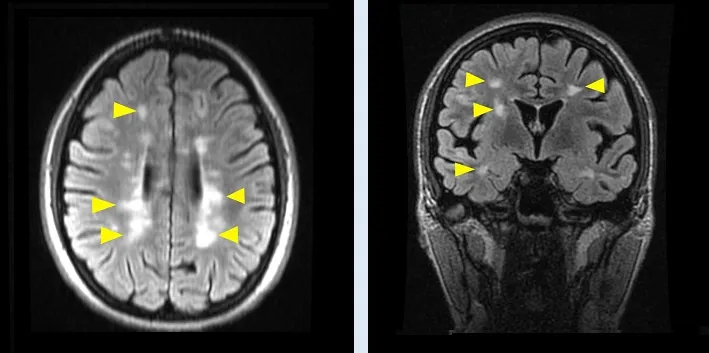

Σκλήρυνση κατά πλάκας: Νέα πειραματική θεραπεία από Ομογενή

Μια νέα θεραπεία για την Πολλαπλή Σκλήρυνση, που έχει αναπτυχθεί από την ομάδα του ομογενούς νευροεπιστήμονα Στήβεν Πετράτος στο Πανεπιστήμιο Monash, δίνει ελπίδες σε εκατομμύρια ασθενείς παγκοσμίως. Η πειραματική θεραπεία, με την ονομασία Diaprotectome, έχει σχεδιαστεί ώστε να επιδιορθώνει τις βλάβες στο Κεντρικό Νευρικό Σύστημα (ΚΝΣ) που προκαλούνται κατά την εξέλιξη της νόσου, προσφέροντας διπλή δράση: αφενός αποτρέπει την περαιτέρω καταστροφή της μυελίνης, του προστατευτικού περιβλήματος των νευρώνων, και αφετέρου διεγείρει τη δημιουργία νέας μυελίνης.

Οι προκλινικές δοκιμές, που έγιναν στην Ελλάδα, την Αυστραλία και το Ισραήλ, έδωσαν εντυπωσιακά αποτελέσματα. Ζώα εργαστηρίου που ήταν παράλυτα κατάφεραν να κινηθούν ξανά, υποδηλώνοντας αποκατάσταση της φυσιολογικής λειτουργίας του νευρικού συστήματος. Σύμφωνα με τον Δρ. Πετράτο, η θεραπεία είναι επίσης εύκολη στη χρήση, καθώς πρόκειται για χάπι που μπορεί να λαμβάνεται συμπληρωματικά με τις τρέχουσες θεραπείες.

Στην Ελλάδα, η θεραπεία προγραμματίζεται να δοκιμαστεί μέσω της κλινικής μελέτης «Odyssey», σε συνεργασία με τον καθηγητή νευρολογίας Νικόλαο Γρηγοριάδη του ΑΠΘ. Οι δοκιμές θα διαρκέσουν 12 μήνες και θα διεξαχθούν σε νοσοκομεία ανά την Ελλάδα, με στόχο να συμμετάσχουν έως και 400 ασθενείς με Πολλαπλή Σκλήρυνση. Εφόσον οι κλινικές δοκιμές ολοκληρωθούν με επιτυχία, η θεραπεία θα περάσει σε δοκιμές σε διεθνές επίπεδο και, αν εγκριθεί, θα τεθεί σε μαζική παραγωγή, προσφέροντας μια πολλά υποσχόμενη νέα επιλογή για τους ασθενείς με Πολλαπλή Σκλήρυνση.